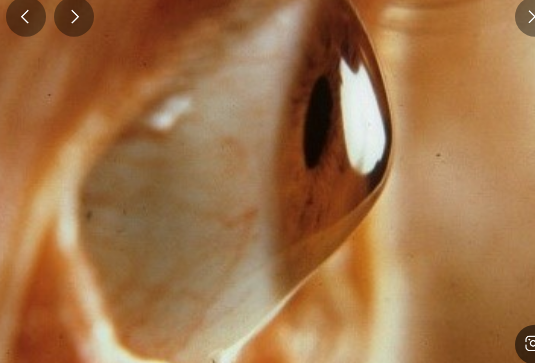

원추각막은 각막이 원뿔 모양으로 변형되어 발생하는 시력장애입니다. 각막은 눈의 앞부분을 덮고 있는 투명한 조직이며, 빛을 굴절시켜 망막에 상을 맺게 하는 역할을 합니다. 원추각막이 발생하면 각막이 비정상적으로 얇아지면서 돌출되어 부정난시가 발생하는 진행성 질환입니다.